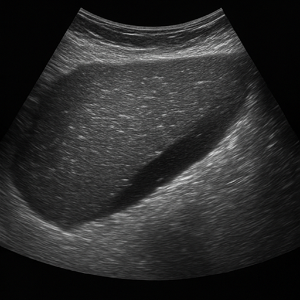

복부 종양과 복수

- 복부 종양(낭종, 종양)

간, 신장, 또는 다른 복부 장기에 생긴 혹들은 초음파에서 덩어리로 보여요. 가끔은 원래 장기가 아닌 곳에 생긴 종양도 보여요. - 복수 (복강 내 물)

배에 물이 고이는 현상이에요. 초음파로 액체가 있는 곳을 쉽게 볼 수 있어서, 복수가 있는지 확인할 때 매우 유용해요.